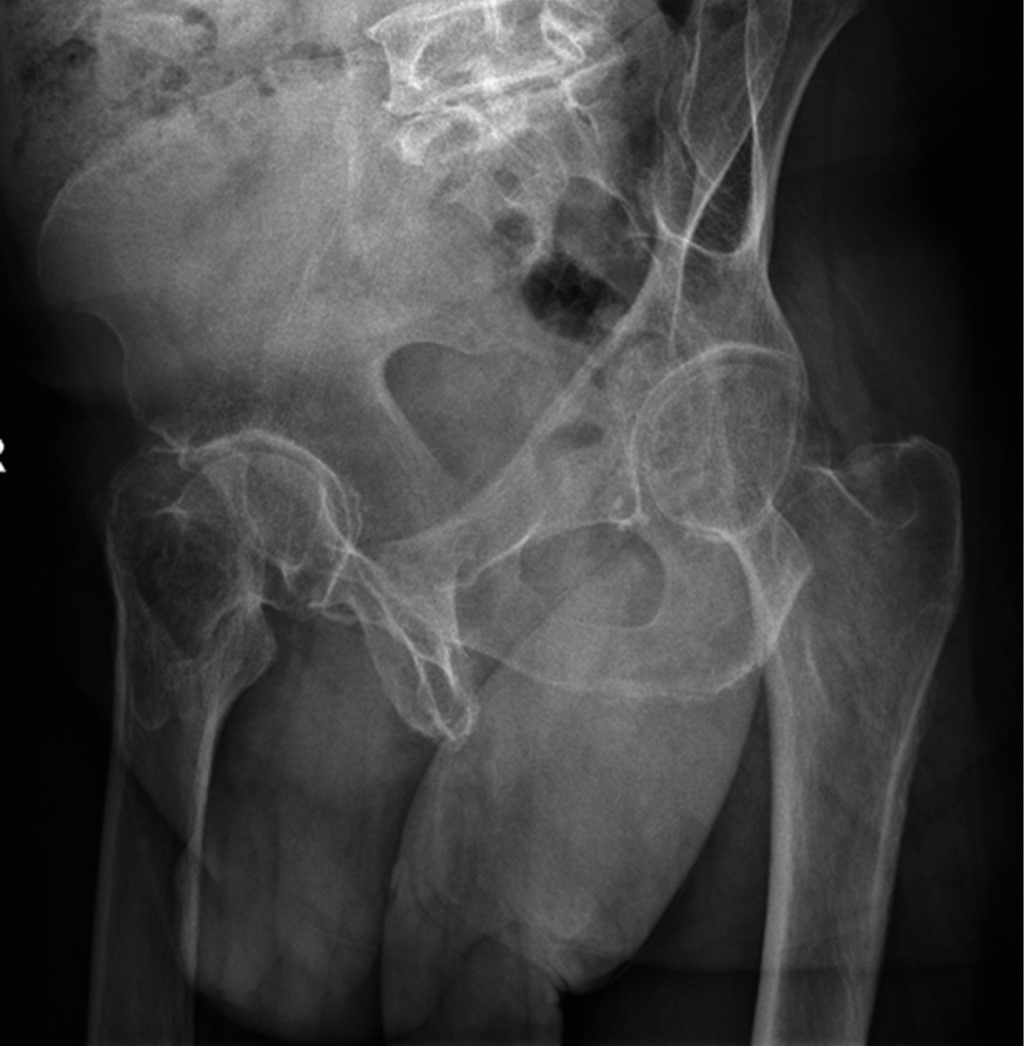

Figure 2

The painful hip has been a topic of study that has evolved from the beginning of the last century to the present. The clinical approach is complex, and requires a systematization process associated with good questioning, clinical maneuvers with their corresponding interpretation, and complementary imaging studies. The understanding of hip pathology, especially in young adults, is highly simplified and sometimes underdiagnosed, therefore, not treated in a timely manner. The prevalence of painful hip is more common in males (49 to 55%) than in females (25 to 28%), and the causes may vary according to demographic characteristics and the history of each patient. Bryan Kelly, made a topographic and anatomical description of the approach to the painful hip according to the theory or system of the layers: I. Osteochondral layer; II. Inert layer; III. Contractile layer; and IV. Neuro-mechanical layer. This system helps us understand the anatomical site of pain and its clinicopathological correlation. The semiological approach to hip pain is the fundamental pillar for differential diagnosis. We can divide it according to its topography into anterior, lateral and posterior, as well as according to its chronology and characteristics. The physical examination should be carried out systematically, starting from a generalized inspection of gait and posture to the evaluation of specific signs for alterations in each layer, which evoke pain with specific postures and ranges of mobility, or weakness and alterations in the arc of mobility of the joint. Image evaluation is initially recommended with radiographic projections that evaluate different planes, both coronal, sagittal and axial, complemented with panoramic views, and eventually dynamic sagittal ones if necessary. Requesting specific studies such as tomography to evaluate bone structure and reserve, or simple MRI when there is suspicion of soft tissue affection, or failing that, arthroresonance for joint pathology, will depend on the clinical symptoms and radiographic findings.